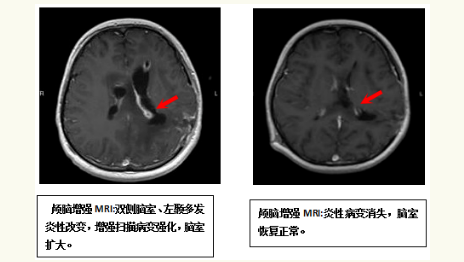

我科与“付继弟颅内感染诊疗团队”进行了密切合作,成立了“中枢神经系统感染诊治中心”,已经成功开展了各种原因引起的颅内、椎管内顽固性严重感染性,和相关神经重症疾病的诊断与治疗,收治的病人来自京外各地医院转来的重症患者。付继弟教授、潘栋超医生亲自参与我科病人的手术及围手术期管理和诊疗工作,经治疗的患者病情均得到有效的转规,好转出院。

我科与首都医科大学附属北京胸科医院建立技术合作,联合“付继弟颅内感染诊疗团队”共同组建了由张立群教授、付继弟教授、张蓬川主任医师、潘栋超和何刚副主任医师组成的“中枢神经系统结核病诊疗团队”,成立了“中枢神经系统结核病诊治中心”,形成了针对“中枢神经系统结核性疾病”的内外科全面系统的诊断及治疗体系,病情均得到有效治疗,病人好转出院。